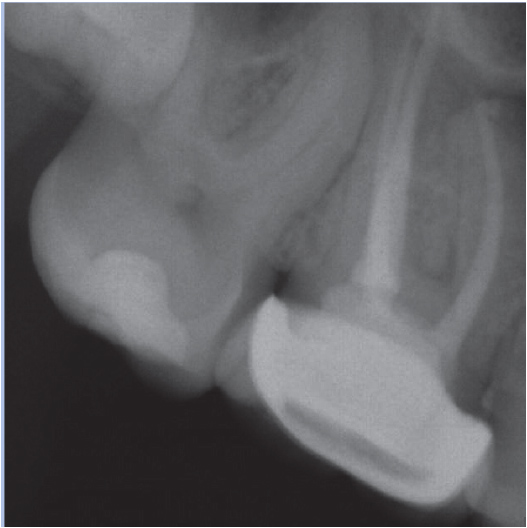

Before

After

Before Root Canal treatment

After Root Canal treatment